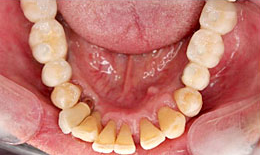

治療後

下顎

インプラントを7本埋め込んで、セラミックスクラウンを被せた